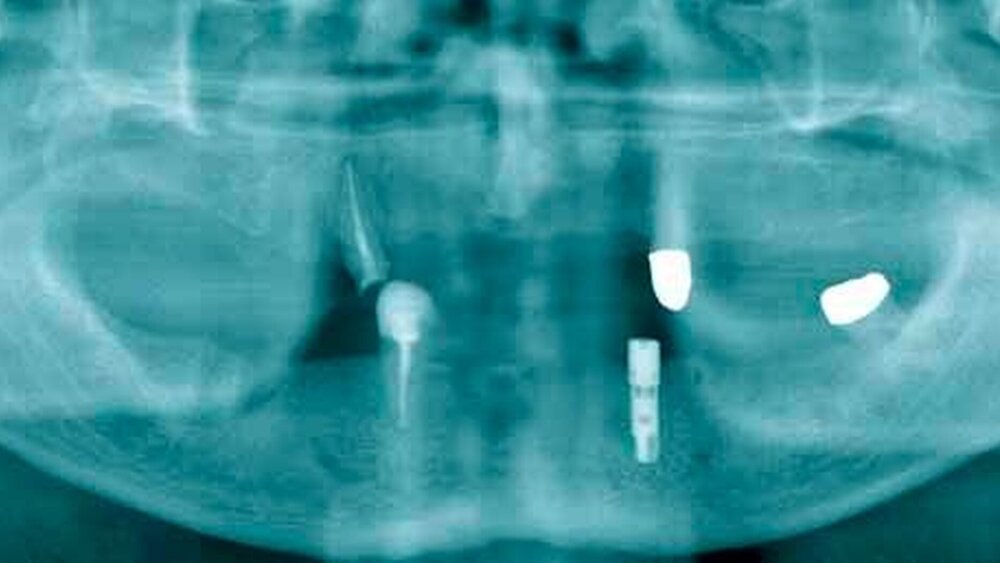

Die Kooperation der Klinik für Zahn-, Mund- und Kieferheilkunde mit der Firma Nobel Biocare (Schweden) ermöglichte es, den Patienten Implantate und die prothetische Versorgung zu einem reduzierten Preis anzubieten. Den Studenten wurde auf diese Weise nicht nur der theoretische Hintergrund der oralen Implantologie in Vorlesungen und Seminaren vermittelt, sondern auch das praktische Vorgehen am Patienten unter Anleitung eines Assistenzarztes durchgeführt. Im Folgenden soll anhand von zwei Patientenfällen (Fall 1: Freiendsituation, Abbildung 1; Fall 2: Hybridprothetik, Abbildung 1) die Diagnostik, Planung und das Setzen der Implantate durch die „studentische Hand“ vorgestellt werden.

Basierend auf dem Wax-up/Set-up wird eine Röntgenschiene aus PMMA-Kunststoff hergestellt und mit Guttaperchamarkern versehen. Die Ausdehnung der Schiene richtetsich nach dem Restzahnbestand. Nun folgt die radiologische Untersuchung. Es werden zwei DVT- oder CT-Datensätze erstellt; einer mit dem Patient und der Röntgenschiene, ein zweiter mit der Schiene alleine.

Mit den gewonnen radiologischen Daten kann die Planung mit der NobelGuide™ Software (Fall 1, Abbildung 3; Fall 2, Abbildung 2) vorgenommen werden. Der Student plant zusammen mit seinem Assistenten Position, Länge und Durchmesser der Implantate. Mit diesen Planungsdaten wird von Nobel Biocare über ein stereolithographisches Verfahren eine Bohrschablone (Fall 1 ,Abbildung 2; Fall 2, Abbildung 3) erstellt, mit welcher eine geführte Implantation möglich ist.

Die Studenten können unter Anleitung ihres Assistenzarztes die Implantation selbst durchführen (Fall 1, Abbildungen 5 bis 7; Fall 2, Abbildungen 4 bis 6).